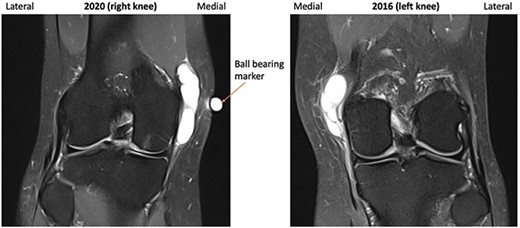

A repeat MRI was performed and reported ‘very similar’ appearances to the left knee, showing a septated ganglion originating from the postero-medial aspect of the joint and subchondral cyst formation with a pattern and location mirroring that which had involved the left knee (Figs 1–3). Reassured by these findings, the patient deferred surgery.

2016 and 2020 T2-weighted MRI in coronal plane with ganglion cyst visible medially.